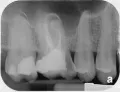

Удалили зуб пятерку. Ортопед сказал, что нужно делать мост на два зуба по краям: четверку и шестерку.

Шестой зуб сильно проелся и был почти у самой десны, врач сообщил, что нужно делать вкладку. Но в этом зубе стоял штифт и большая пломба, когда он начал всё высверливать и убирать, оказалось, что у меня там два открытых канала, которые впоследствии запломбировала врач-ортопед.

На четвертом зубе у меня стоит тоже пломба и штифт, маленький кусочек пломбы откололся. Поскольку зуб не проелся, врач говорит, что его не нужно трогать и сразу будут готовить под коронку.

Прав ли врач? Или же нужно тоже его проверить на состояние каналов?

Смените доктора, перед протезированием ортопед обязан провести анализ корневых каналов методом рентген-контроля, определить необходимость пролечить и установить культевую вкладку, и только потом коронку.